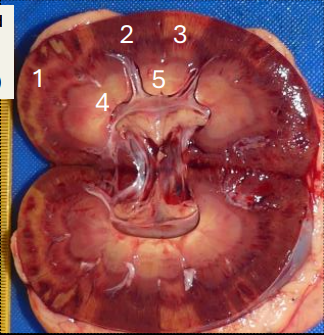

What does this image show?

cut surface of the abnormal kidney

What areas or the kidney, labelled as 1-5 are abnormal?

1&3

What has occurred in the areas highlighted?

obstruction to blood supply that restricts blood supply to paler areas

What type of change has occurred in the renal parenchyma?

coagulative necrosis